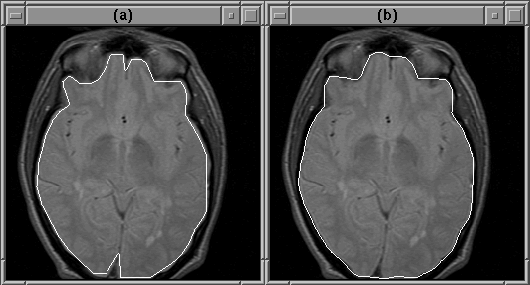

Figure 8.22: (a) Brain tissues in slice 11 of MRI Data Set 2 identified by a radiologist. (b) The automatically detected intracranial boundary.

Figure 8.22 shows the regions in slice 11 that a radiologist identified as brain tissue. At least for slice 11, the automatically detected intracranial boundary appears to outline the brain accurately.